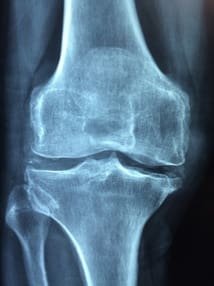

Gonarthrose, quoi de neuf ce mois-ci ?